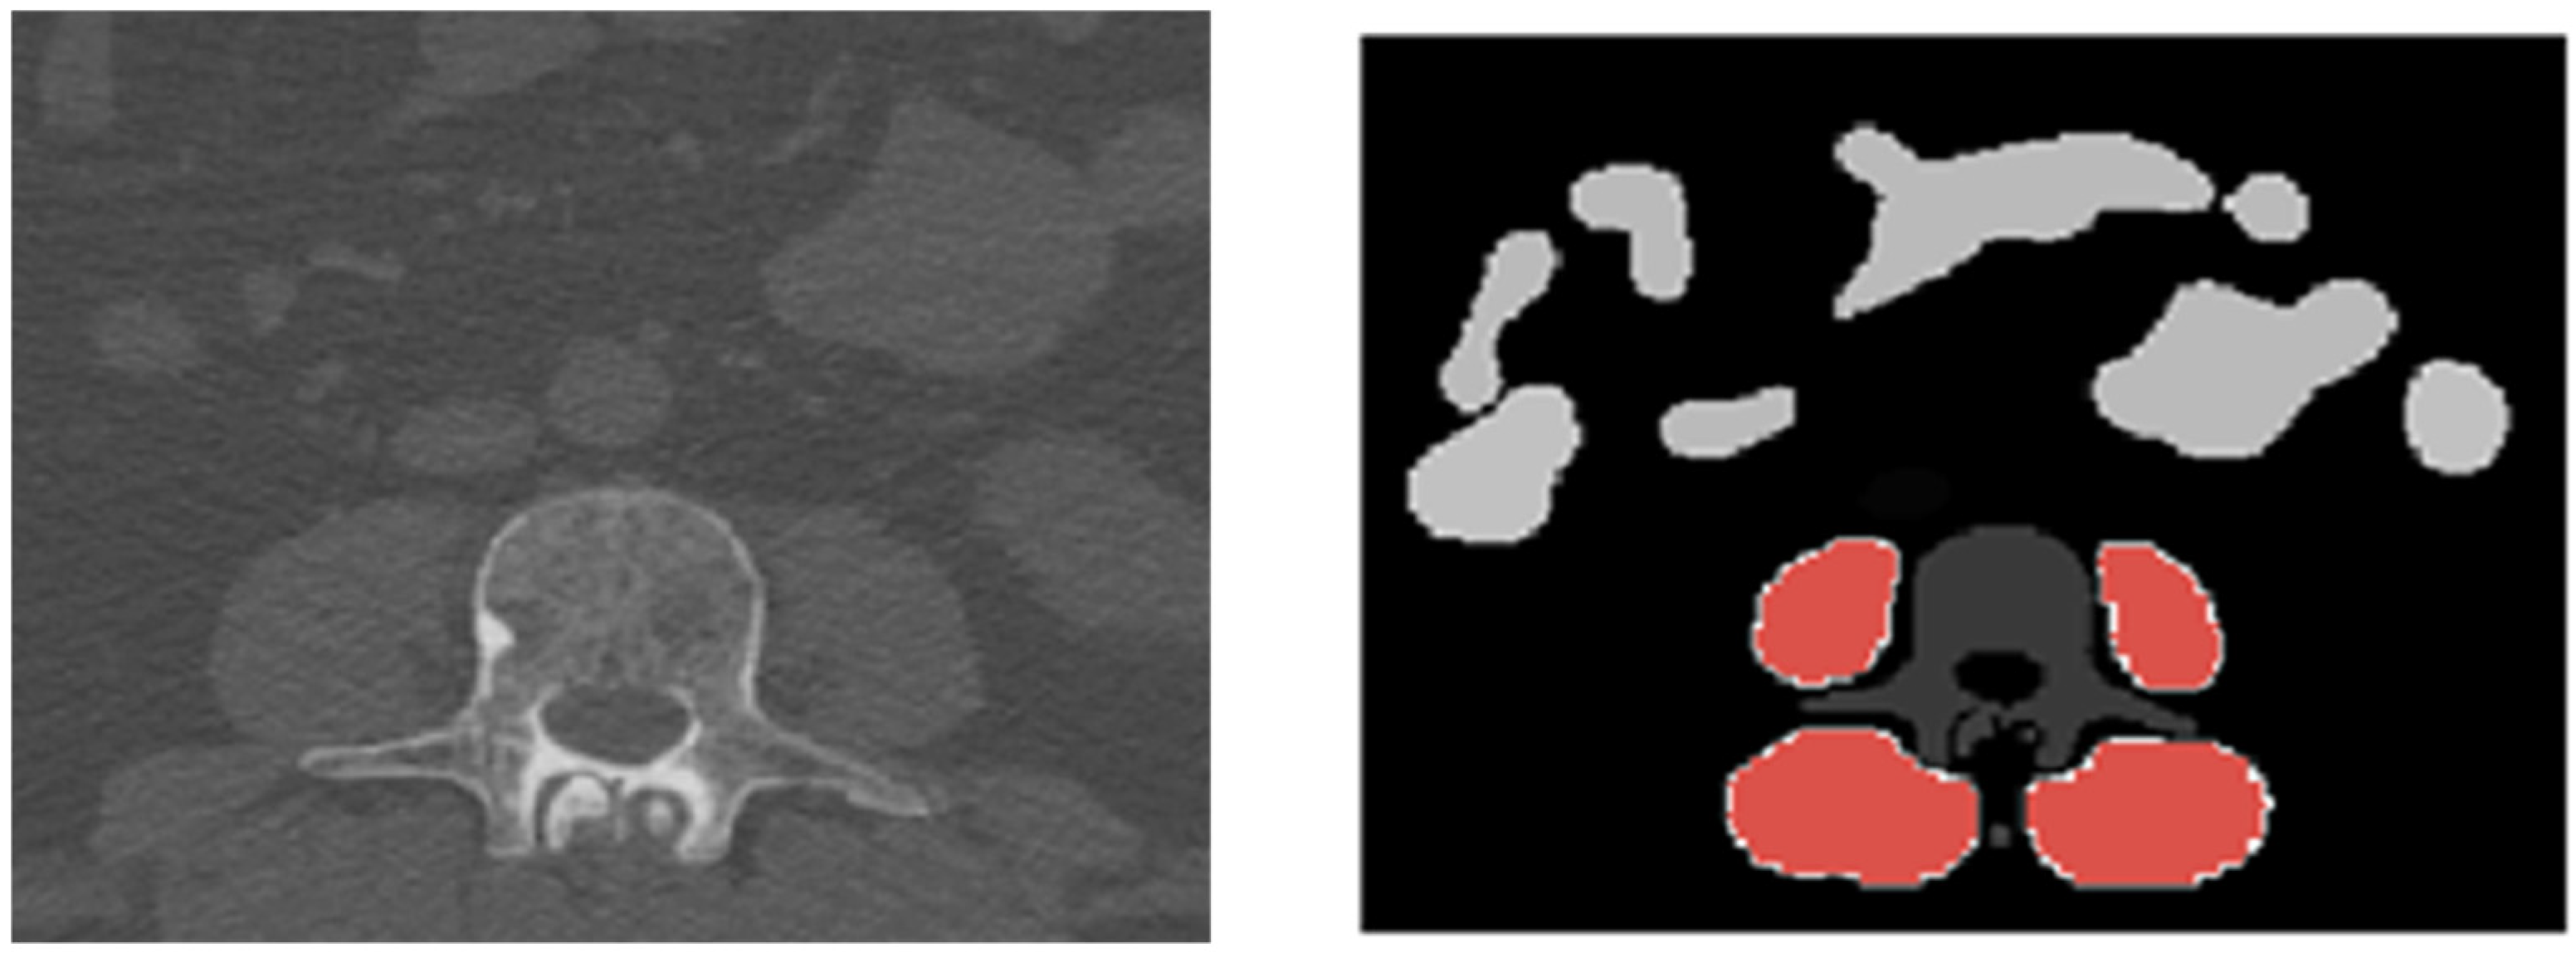

2.4. Segmentation

- Koitka, S.; Kroll, L.; Malamutmann, E.; Oezcelik, A.; Nensa, F. Fully automated body composition analysis in routine CT imaging using 3D semantic segmentation convolutional neural networks. Eur. Radiol. 2021, 31, 1795–1804. [Google Scholar] [CrossRef] [PubMed]